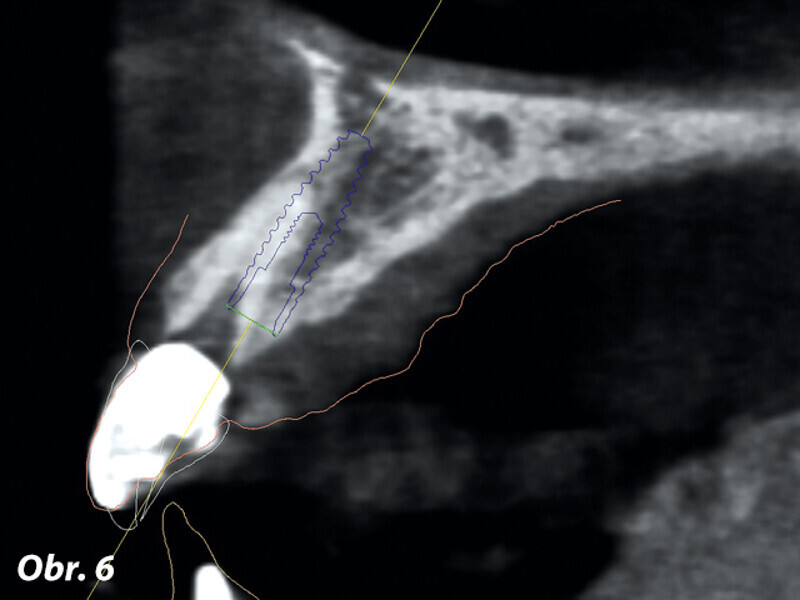

Imediátní zavedení a zatížení implantátu 2